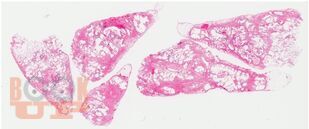

В учебном пособии рассматриваются актуальные и современные вопросы диагностики и лечения интерстициальных заболеваний легких.